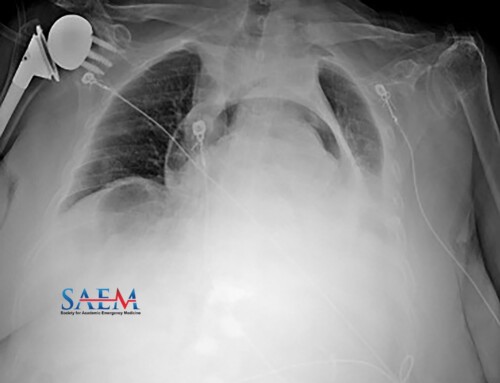

PV Card: Upper GI Bleed

Adapted from [1, 2]